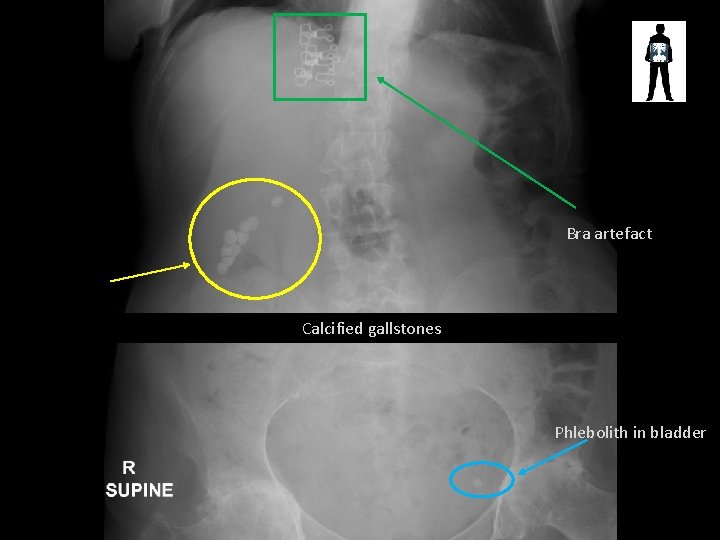

Bra artefact Calcified gallstones Phlebolith in bladder

Air in stomach STAGHORN CALCULUS Complete obstruction of the renal pelvis Bladder phlebolith